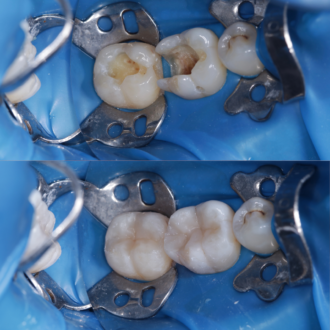

- Розтин зуба, видалення уражених карієсом тканин та доступ до кореневих каналів.

- Видалення інфікованої пульпи з камери та каналів, розширення каналів за допомогою спеціальних інструментів. Це найскладніший етап лікування кореневих каналів, коли використовуються інструменти діаметром менше міліметра (наприклад, 0,08 мм).

- Реконструкція зуба, наприклад, шляхом композитної реставрації або встановлення керамічної коронки.